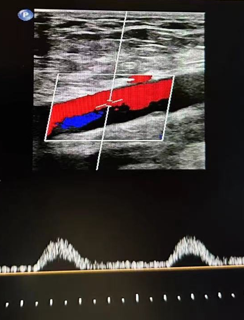

心功能室的李月醫(yī)生在檢查時敏銳捕捉到異常信號:雙側(cè)股總動脈血流頻譜呈特征性“小慢波”——這通常是大血管嚴重狹窄的強烈提示。

然而,蹊蹺之處隨之浮現(xiàn)。醫(yī)生仔細掃查了患者從股動脈直至腹主動脈的整條下肢供血通路,血管結(jié)構(gòu)清晰,未見明顯狹窄或斑塊。

經(jīng)驗豐富的醫(yī)生判斷問題可能潛藏在更近心端的胸主動脈,但該區(qū)域受胸骨遮擋,常規(guī)超聲探查受限。

心功能室王璇主任會診后,結(jié)合異常血流動力學特點,將目標鎖定超聲探查難點——胸骨遮擋的降主動脈胸段!建議行主動脈CT血管成像(CTA)檢查以明確診斷。

CTA結(jié)果印證了王璇主任的判斷:患者降主動脈胸段(距鎖骨下動脈約10厘米處)存在一處少見的先天性局部縮窄,并伴有遠端擴張。這正是導致患者下肢血流灌注不足、多年感覺發(fā)涼的“元兇”——降主動脈縮窄,一種少見的血管發(fā)育畸形!